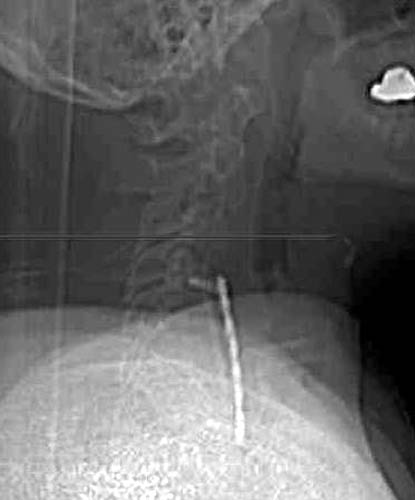

Scout image from a CT 3 month later suggests ventral displacement of the

bone graft and fixation plate. |